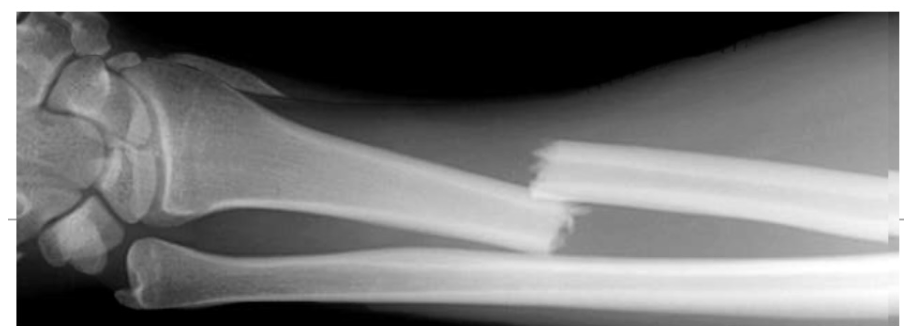

polsfractuur:

Wanneer conservatief?

Wanneer operatief?

Stabiel, niet-verplaatst → gips.

Instabiel

Intra-articulair

Slechte repositie

belangrijkste complicaties polsfractuur

Compartimentsyndroom

Carpaal tunnelsyndroom

CRPS

Zenuwschade